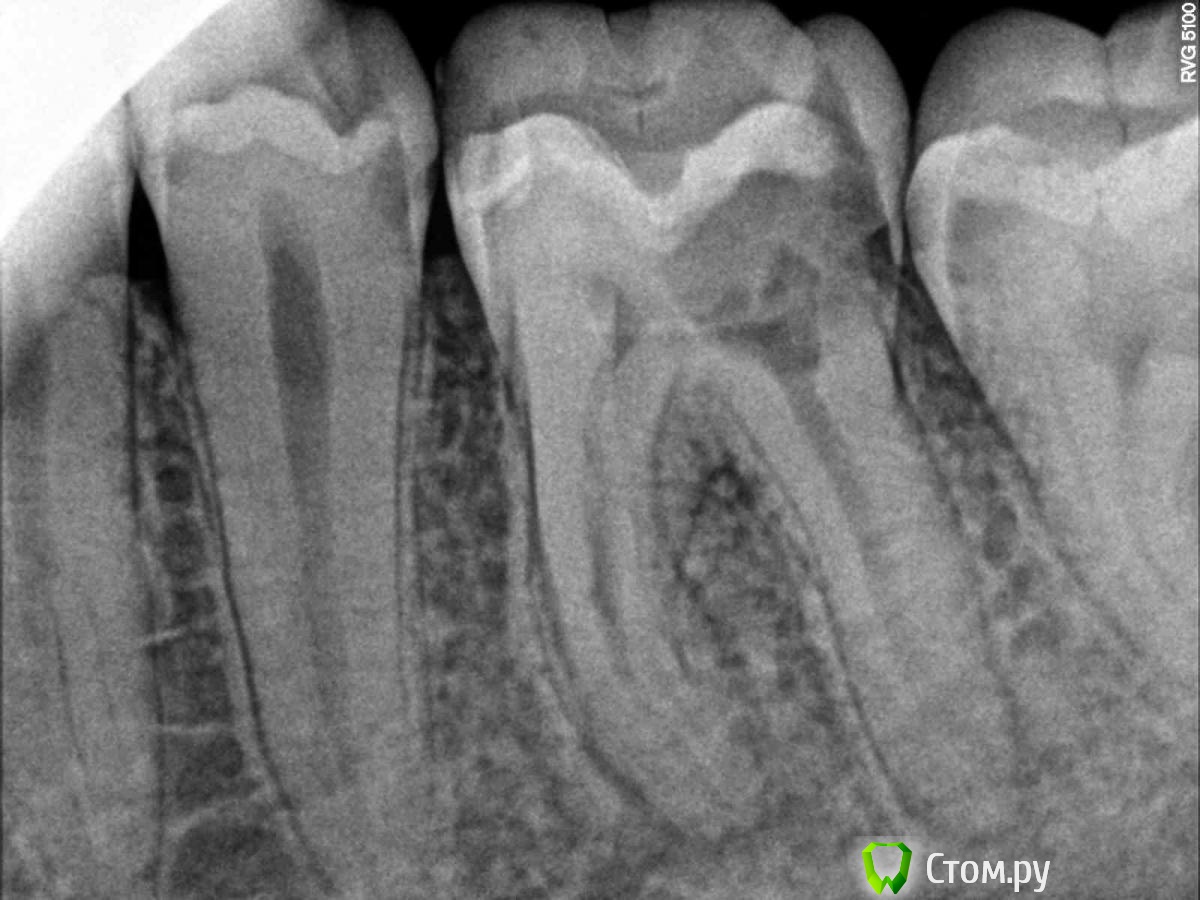

Польский Антон Опубликовано 23 июля, 2014 Поделиться Опубликовано 23 июля, 2014 на снимке киста в бифуркации, есть ли шанс на этой стадии вылечить антибиотиками или хирургическим вмешательством без удаления зуба? Ссылка на комментарий

Польский Антон Опубликовано 23 июля, 2014 Автор Поделиться Опубликовано 23 июля, 2014 вот есть в таком варианте Ссылка на комментарий

red_butler Опубликовано 23 июля, 2014 Поделиться Опубликовано 23 июля, 2014 (изменено) Другое дело, зубу требуется эндодонтического лечение с последующим протезированиемИ оба соседних лечите Изменено 23 июля, 2014 пользователем red_butler 1 Ссылка на комментарий

Польский Антон Опубликовано 23 июля, 2014 Автор Поделиться Опубликовано 23 июля, 2014 а что это за потемнение в десне между корнями? Ссылка на комментарий

Evikrol Опубликовано 23 июля, 2014 Поделиться Опубликовано 23 июля, 2014 более пористая кость. Это не киста. Ссылка на комментарий

IvanK Опубликовано 23 июля, 2014 Поделиться Опубликовано 23 июля, 2014 Таков рисунок костной ткани. Ссылка на комментарий

Bier Опубликовано 26 июля, 2014 Поделиться Опубликовано 26 июля, 2014 меня больше смущает кариозная полость на уровне кости. Ссылка на комментарий

diesel87 Опубликовано 26 июля, 2014 Поделиться Опубликовано 26 июля, 2014 меня больше смущает кариозная полость на уровне кости.Мне кажется это угол съемки такой Ссылка на комментарий